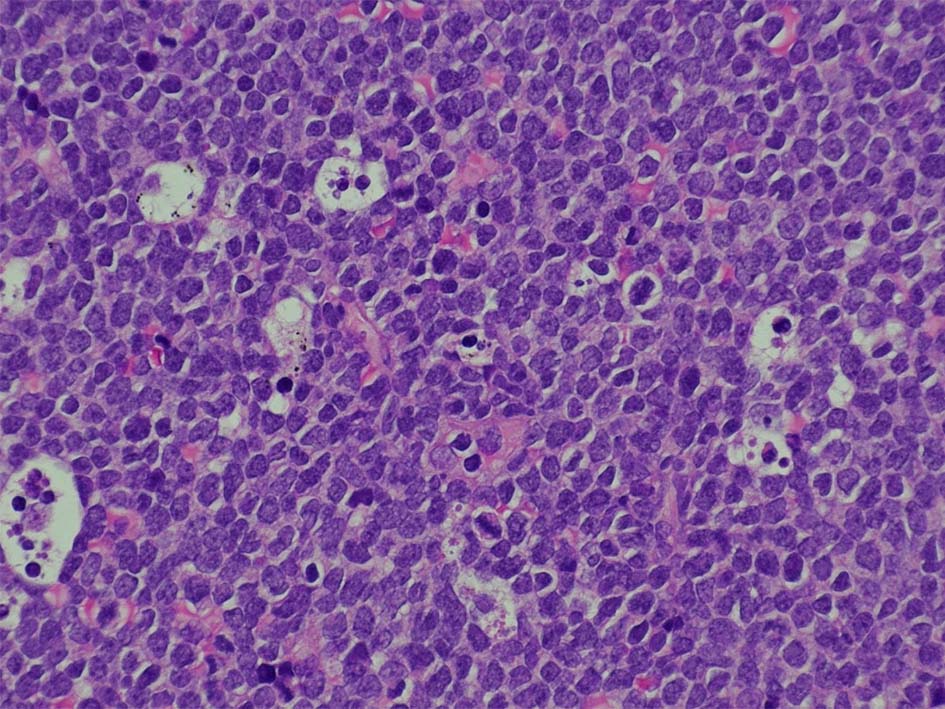

T-lymphoblastic leukaemia/ lymphoma

Tリンパ芽球性白血病/リンパ腫、NOS( WHO5th classification*1)

T-ALL/LBL 縦隔腫瘍, 胸水貯留症例

70歳男性 KNS

右肺上葉から前縦隔に90mm大の腫瘤あり. 右胸水貯留を伴う. 右主気管支よりEBUS-TBNAをおこなう.